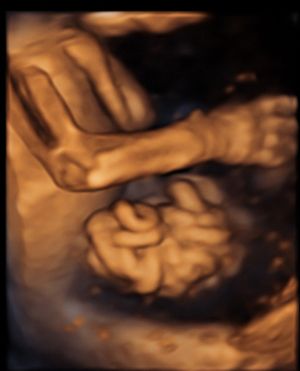

Im Rahmen des Ersttrimester-Screenings untersuchen wir die Organe des Feten mittels Ultraschall. Dabei machen wir auch gerne ein Bild für Sie.

Obwohl der Fet zu diesem Zeitpunkt erst zwischen 5 und 8cm groß ist, lassen sich bereits etwa die Hälfte aller schwerwiegenden Fehlbildungen erkennen bzw. ausschließen. Sollten wir eine Auffälligkeit sehen, werden wir mit Ihnen den Befund und das weitere Vorgehen ausführlich besprechen.

Fetale Anatomie